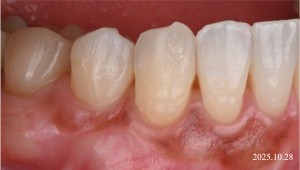

After

完全に根面が歯肉によって被覆されている。

※術後約5ヶ月経過時

術後の経過について

術後の経過を確認したところ、露出していた歯の根の部分は歯ぐきによって覆われ、良好な状態が得られました。

また、手術に伴う歯ぐきの瘢痕(きずあと)も目立ちにくく、比較的自然な歯ぐきの形態を保つことができました。

治療後には、患者様からも見た目の改善についてご満足いただけたとのお言葉をいただきました。

※根面被覆後約5年

術後の長期経過について

現在、根面被覆術を行ってから約5年が経過していますが、歯ぐきの状態は安定しており、良好な経過を保っています。

今回の症例では、結合組織移植術を併用して歯ぐきの厚みを増やす処置を行いました。歯ぐきの厚みを改善することは、歯ぐきの安定性を高める要因の一つと考えられています。

その結果、現在のところ歯ぐきの再退縮は認められず、比較的良い状態を維持しています。

今後も、定期的なメンテナンスを行いながら、歯ぐきの状態を確認していく予定です。